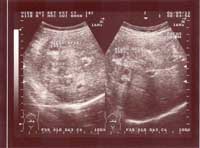

Một số hình ảnh siêu âm tổn thương gan do sán lá gan lớn:

Hình ảnh 5: Khối tổn thương sán lá gan không điển hình (ở giai đoạn sớm): Một khối tăng âm không đồng dạng, giới hạn ít rõ | Hình ảnh 6: Khối tổn thương gan do SLGL không điển hình: Một khối lớn tăng âm không đồng dạng, dễ nhầm với hình ảnh một khối u gan |